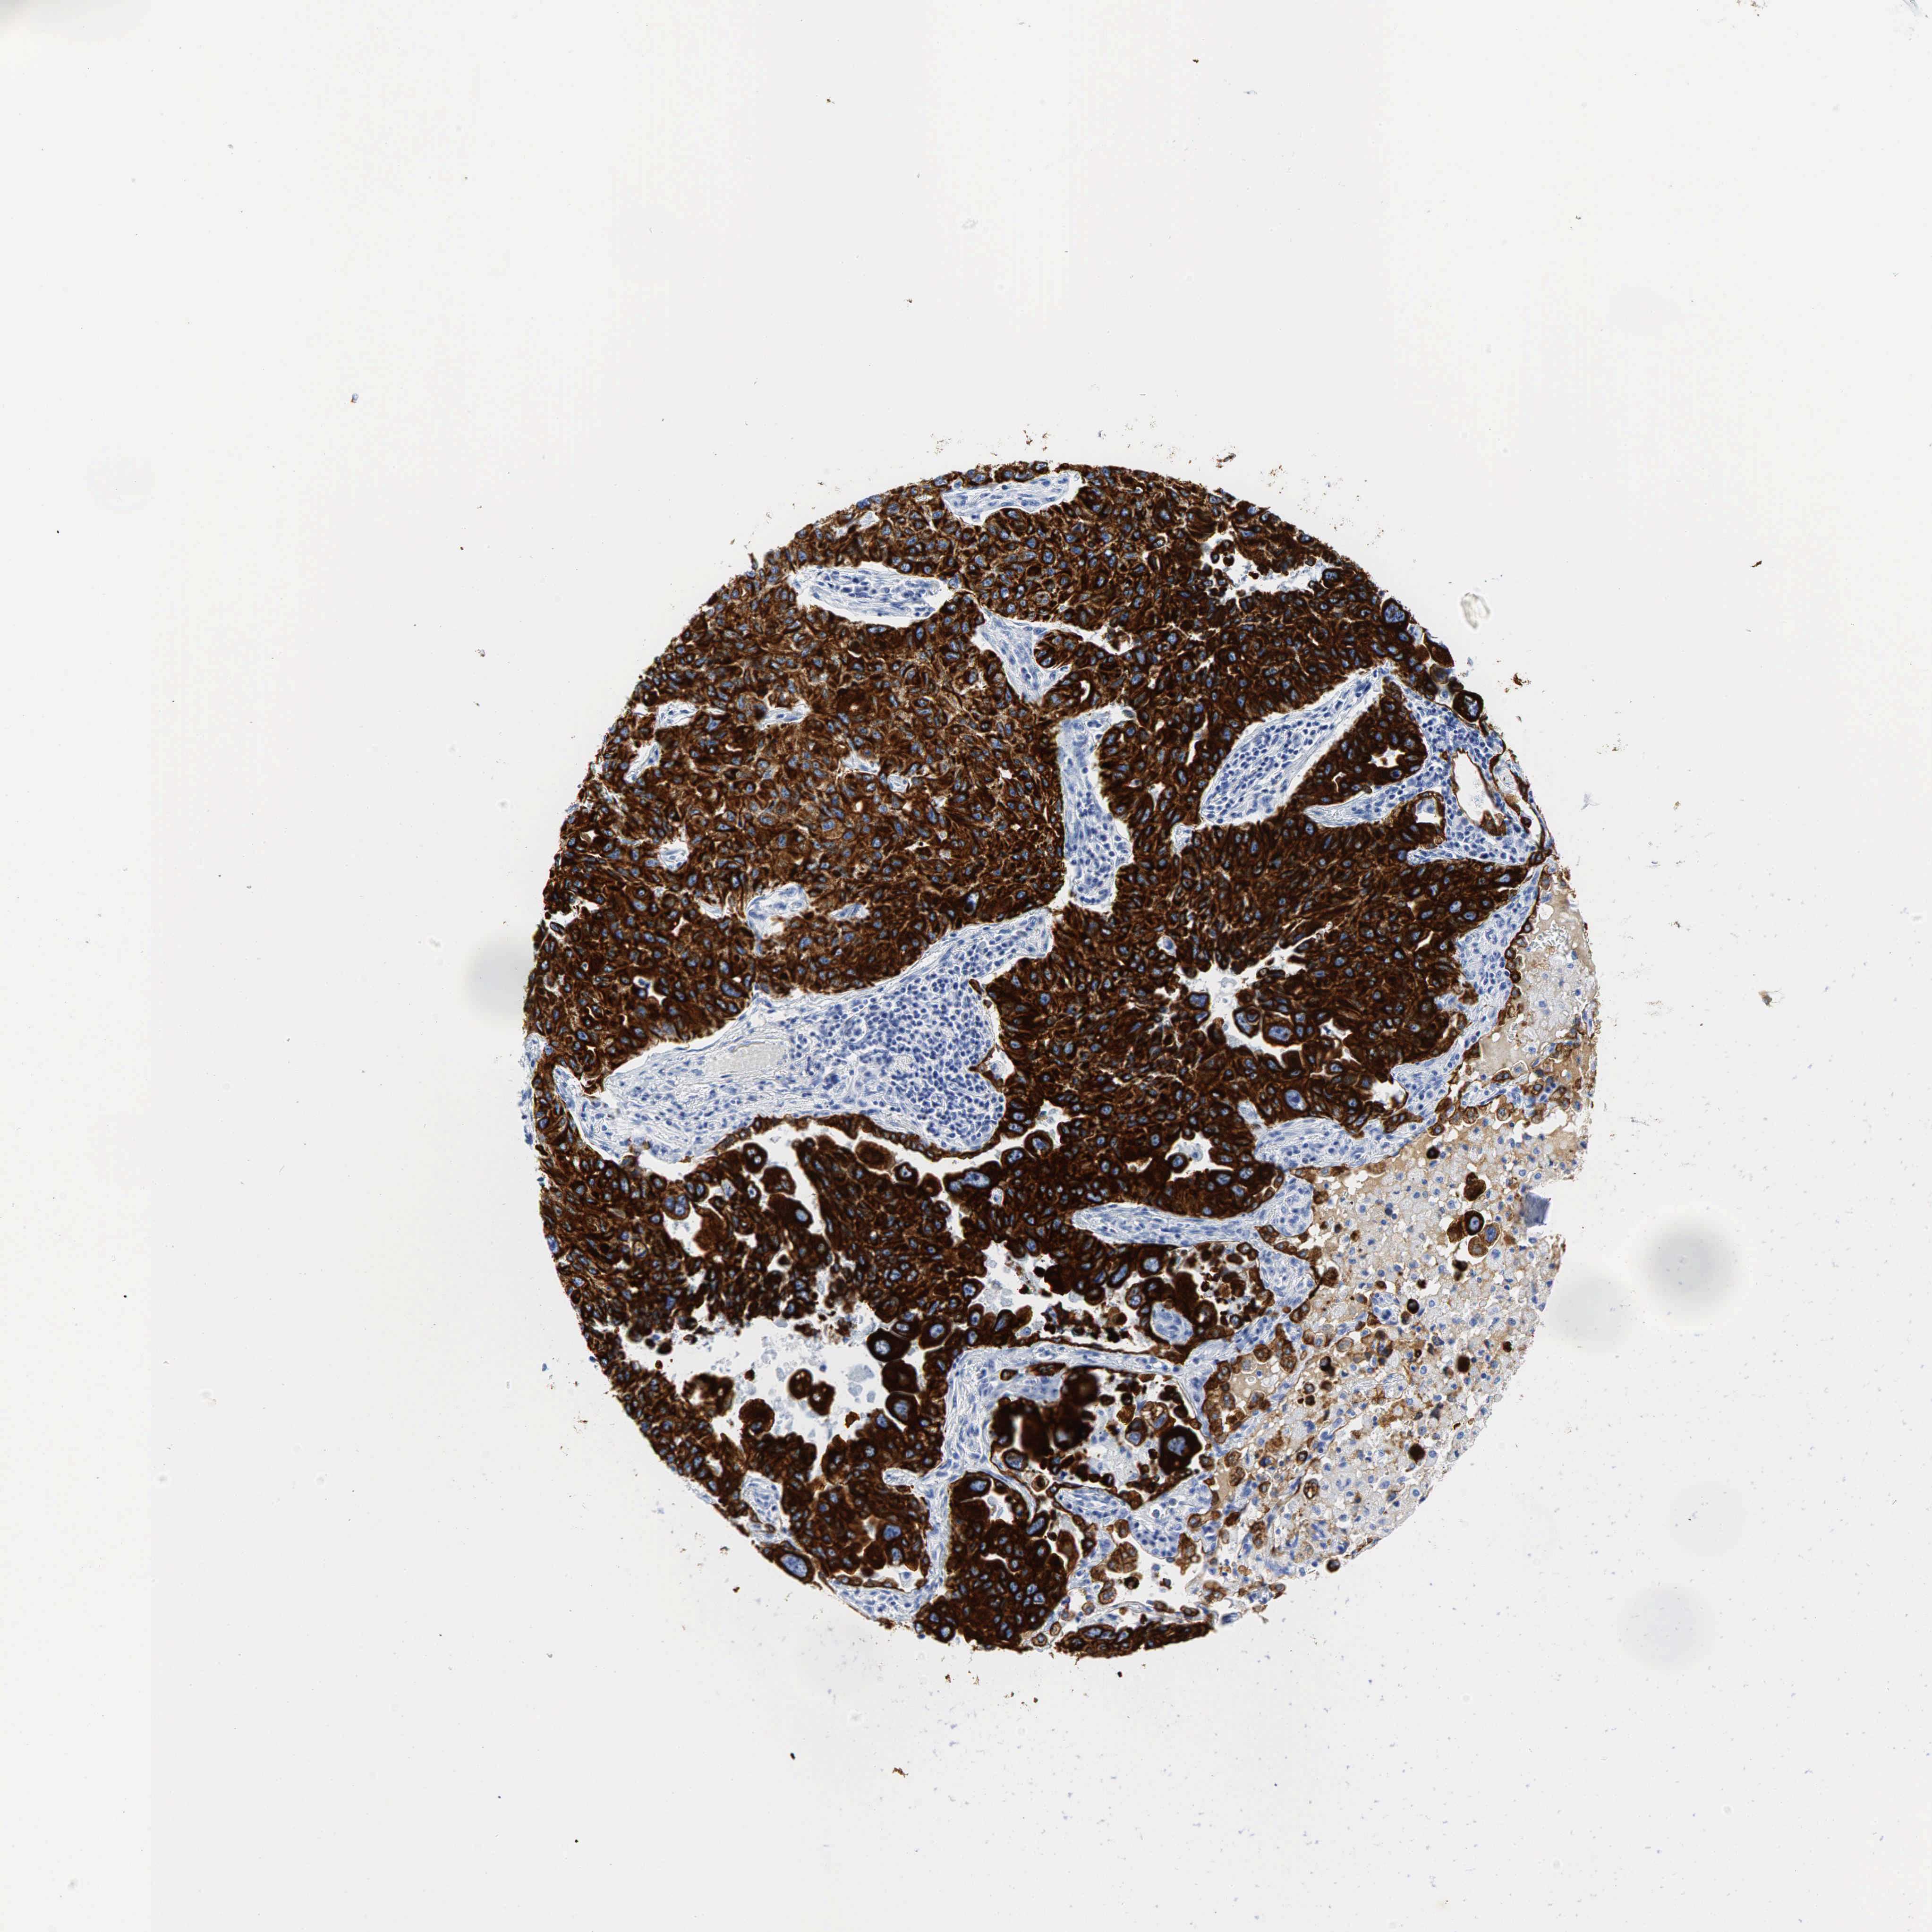

LUNG SQUAMOUS CELL CARCINOMA (TCGA) - Interactive survival scatter ploti

The Survival Scatter plot shows the clinical status (i.e. dead or alive) for all individuals in the patient cohort, based on the same data that underlies the corresponding Kaplan-Meier plots. Patients that are alive at last time for follow-up are shown in blue and patients who have died during the study are shown in red.

The x-axis shows the expression levels (FPKM) of the investigated gene in the tumor tissue at the time of diagnosis. The y-axis shows the follow-up time after diagnosis (years). Both axes are complimented with kernel density curves demonstrating the data density over the axes. The top density plot shows the expression levels (FPKM) distribution among dead (red) and alive patients (blue). The right density plot shows the data density of the survived years of dead patients with high and low expression levels respectively, stratified using the cutoff indicated by the vertical dashed line through the Survival Scatter plot. This cutoff is automatically defined based on the FPKM cutoff that minimizes the p-score. The cutoff can be changed by dragging the vertical line or by entering a cutoff value in the square labeled "Current cut-off".

Under the Survival Scatter plot the p-score landscape (black curve; left axis) is shown together with dead median separation (red curve; right axis). Dead median separation is the difference in median mRNA expression between patients who have died with high and low expression, respectively. It is calculated as follows: median FPKM expression of dead patients with high expression - median FPKM expression of dead patients with low expression. This is intended to aid the user in visually exploring custom cutoffs and the associated p-scores and dead median separation.

Individual patient data is displayed and can be filtered by clicking on one or more of the category buttons on the top of the page. Categories describing expression level and patient information include: high, low, alive, dead, female, male and tumor stages. The scale of the x-axis can be toggled between linear and log-scale by clicking on the "x log" button. Mouse-over function shows TCGA ID, patient information and mRNA expression (FPKM) for each patient.

& Survival analysisi

Kaplan-Meier plots summarize results from analysis of correlation between mRNA expression level and patient survival. Patients were divided based on level of expression into one of the two groups "low" (under cut off) or "high" (over cut off). X-axis shows time for survival (years) and y-axis shows the probability of survival, where 1.0 corresponds to 100 percent.

KRT18 is not prognostic in Lung Squamous Cell Carcinoma (TCGA)

: 412.68